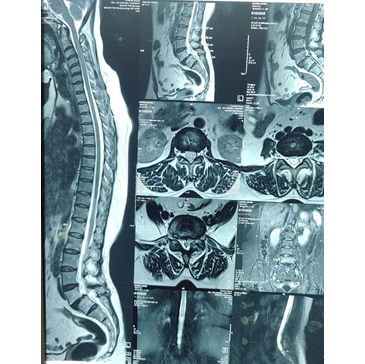

• Imaging tests to identify affected spinal area

• Diagnostic imaging to evaluate spine condition

Spine pain evaluation

How do doctors diagnose spine problems before recommending surgery?

Diagnosis typically includes clinical examination and imaging such as X-ray, MRI, or CT scan.